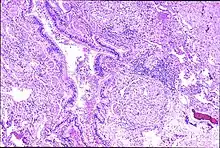

Peribronchal non-necrotizing granuloma from berylliosis

With single or prolonged exposure by inhalation the lungs may become sensitized to beryllium. Berylliosis has a slow onset and progression. Some people who are sensitized to beryllium may not have symptoms.[1] Continued exposure causes the development of small inflammatory nodules, called granulomas.[3] Of note, the authors of a 2006 study suggested that beryllium inhalation was not the only form of exposure and perhaps skin exposure was also a cause, as they found that a reduction in beryllium inhalation did not result in a reduction in chronic beryllium disease or beryllium sensitization.[4]

Granulomas are seen in other chronic diseases, such as tuberculosis and sarcoidosis, and it can occasionally be hard to distinguish berylliosis from these disorders. However, granulomas of chronic beryllium disease will typically be non-caseating, i.e. not characterized by necrosis and therefore not exhibiting a cheese-like appearance grossly.[5]

In susceptible persons, beryllium exposure can lead to a cell-mediated immune response. The T-cells become sensitized to beryllium. Each subsequent exposure leads to an immune response involving CD4+ helper T-lymphocytes and macrophages accumulating in the lungs. As this response continues macrophages, CD+4 T-lymphocytes and plasma cells aggregate together to form the noncaseating granulomas.[7][8] When beryllium is phagocytized by macrophages, the beryllium triggers macrophage apoptosis, thereby reducing beryllium clearance from the lungs and eventually resulting in secondary necrosis and lysis.[9] Eventually, the outcome is fibrosis of the lung.[10][11]